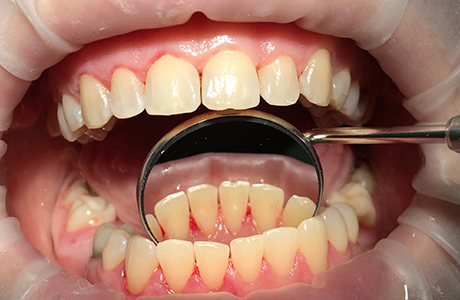

До и после лечения

В «Стоматологию Комфорта» обратилась пациентка с жалобой на твёрдые зубные отложения, которые не поддаются удалению в домашних условиях. В ходе личного осмотра врач стоматолог-терапевт Вахлюева Елена Сергеевна обнаружила зубной камень, затвердевший налёт и назначила пациенту профессиональную гигиену полости рта.

Процесс чистки включал в себя:

- безболезненное снятие твёрдых отложений с помощью ультразвука;

- удаление пигментации от чая, кофе, курения и других красящих продуктов;

- полировку с целью предотвращения новых отложений;

- фторирование зубов с использованием специальных паст для укрепления эмали.